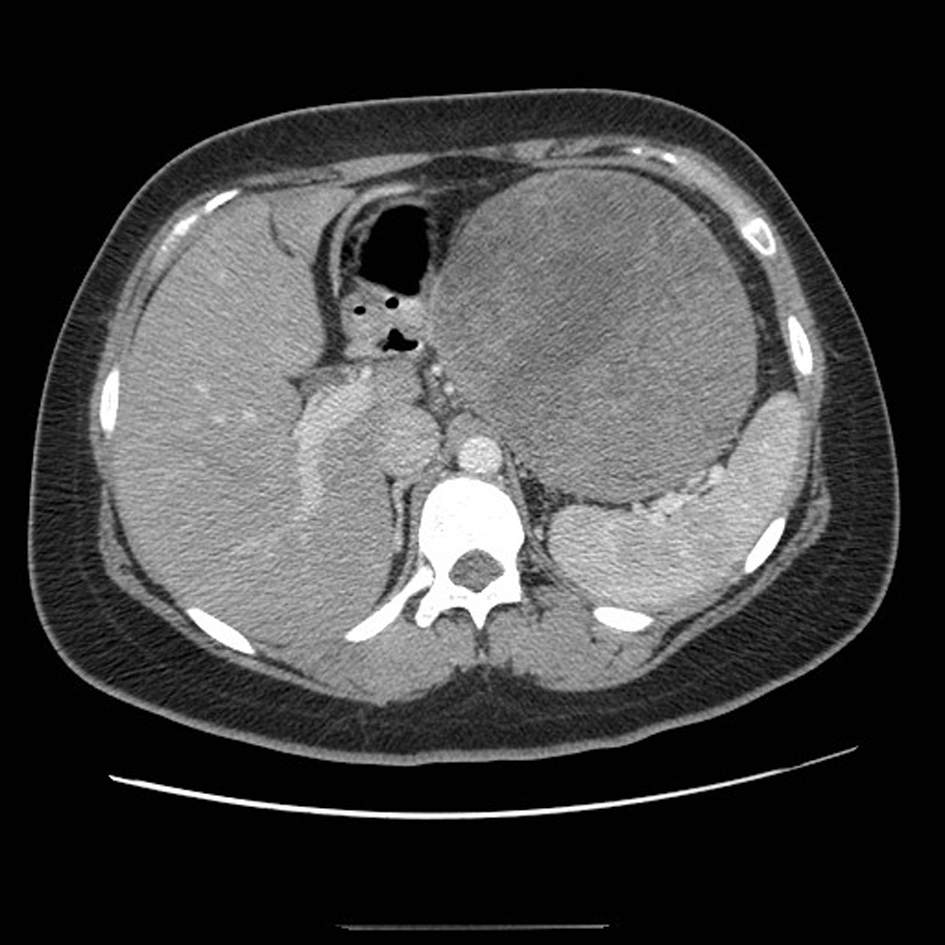

A 21-year-old female patient presented with vague left upper quadrant pain. She did not smoke or consume alcohol, and her only medication was an oral contraceptive. She appeared well, with no abnormal physical exam findings. Routine laboratory studies including liver function tests were all within normal limits. An abdominal ultrasound (AUS) revealed a large mass which appeared to originate from the tail of the pancreas. Computerized tomography-(CT)-scan demonstrated a 12 cm mass arising from the tail of the pancreas and no evidence of metastases (Fig. 1). The patient was taken to the operating room where an exploratory laparotomy confirmed that the large mass arose from the tail of the pancreas. There was no evidence of peritoneal or other distant metastases. The tumor was found to be adherent to the posterior wall of the stomach as well as to the greater omentum. A distal pancreatectomy with en-bloc splenectomy, partial gastrectomy and omentectomy was performed (Fig. 2). Pathology revealed a solid pseudopapillary tumor of the pancreas (Fig. 3), with negative resection margins. Thirteen lymph nodes were examined with the specimen, all negative for metastases. The tumor cells were positive for CD10 and alpha 1-antitrypsin, and focally positive for synaptophysin. The tumor was negative for neuron-specific enolase and chromogranin. The patient’s immediate post-operative course was complicated by pneumonia treated with oral antibiotics. She received appropriate post-splenectomy vaccinations, and was discharged home on post-operative day (POD) 7.

![]() Click for large image | Figure 1. CT scan of the abdomen demonstrating a large mass arising from the tail of the pancreas. |